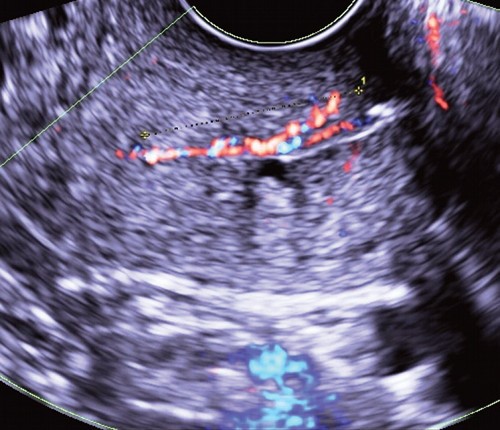

Акустическую основу для возможности проведения неинвазивной эхогистероскопии и эхоцервикоскопии создает серометра, например, в постменопаузальном периоде при обструкции наружного зева (рис. 4) или, как уже было отмечено выше, увеличение продукции шеечной слизи в конце пролиферативной фазы менструального цикла.

Рис. 4. Полип на фоне серометры в постменопаузальном периоде при обструкции наружного зева.